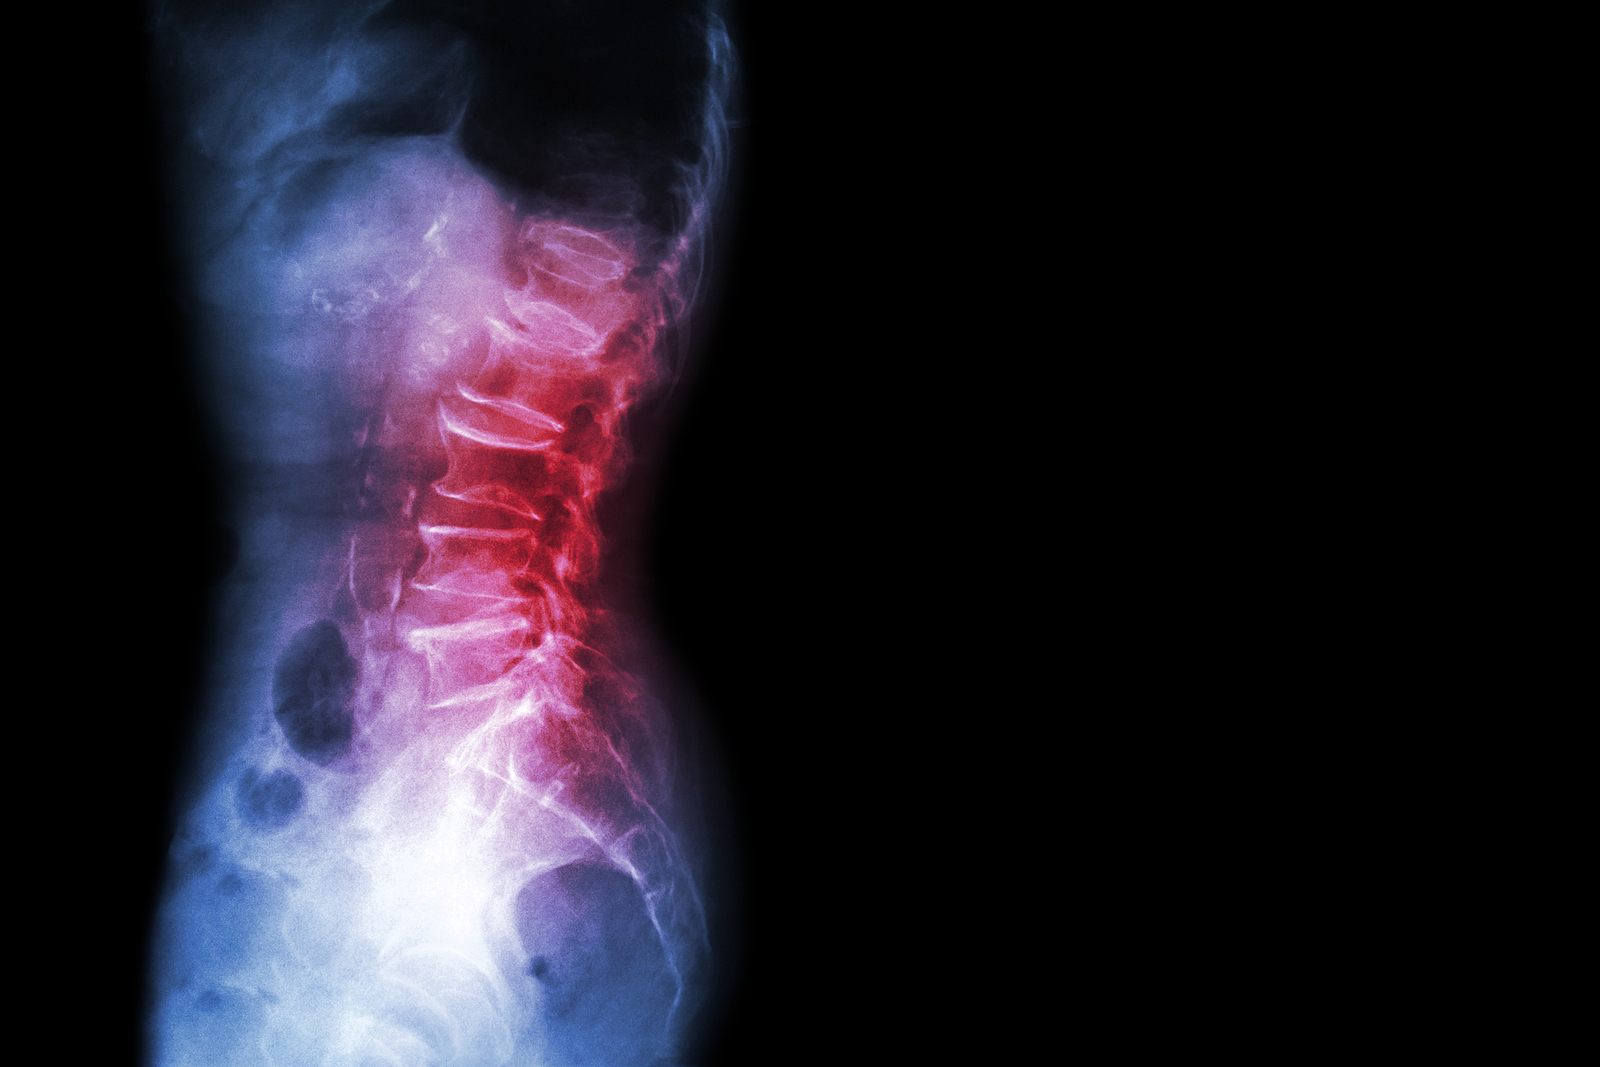

Low Back Pain

Physical therapy in San Marcos for Lower Back

Low back (lumbar) pain is one of the main reasons people visit their doctor. For adults over 40, it ranks third as a major issue—after heart disease and arthritis— that necessitates medical treatment.